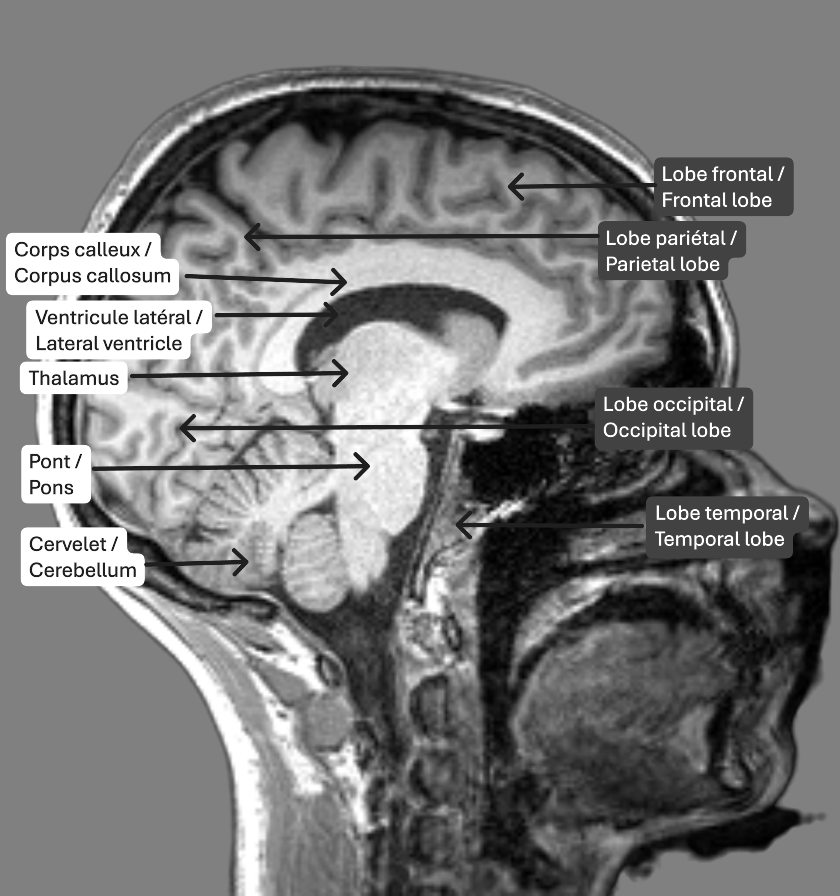

On retrouve trois plans de coupe utilisés dans les images en IRM structurelle, soit les plans axial (transversal) coronal et sagittal. Ce sont différentes façons de sectionner le cerveau qui nous permettent d’observer des structures spécifiques. Le plan axial correspond à un découpage du cerveau du bas vers le haut. Le plan coronal fait référence à des coupes de l’arrière vers l’avant du cerveau. Finalement, le plan sagittal est une façon de diviser le cerveau de la gauche vers la droite.

Identification des structures

Les tissus les plus facilement identifiables sur les images IRM pondérées en T1 sont les ventricules, la matière blanche et la matière grise. Les ventricules, en noir, sont des cavités contenant le liquide cérébrospinal, qui circule également dans les méninges. La matière blanche est constituée des axones des neurones et des connexions entre ceux-ci, et est représentée en gris pâle. En gris foncé, on retrouve la matière grise, qui comprend les corps cellulaires des neurones.

Pilot MRI Data from the Douglas Research Centre